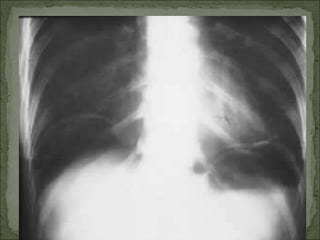

Dor à palpação superficial e profunda de todo o abdome; Resistência abdominal involuntária (abdome “em tábua”); RHA diminuídos ou ausentes; Percussão dolorosa em todo o abdome com desaparecimento da macicez hepática (Sinal de Jobert); Raio-X: pneumoperitônio; Ex: úlcera perfurada, apendicite perfurada, perfuração de delgado ou grosso.

Dor à palpaçãosuperficial e profunda de todo o abdome; Resistência abdominal involuntária (abdome “em tábua”); RHA diminuídos ou ausentes; Percussão dolorosa em todo o abdome com desaparecimento da macicez hepática (Sinal de Jobert); Raio-X: pneumoperitônio; Ex: úlcera perfurada, apendicite perfurada, perfuração de delgado ou grosso.